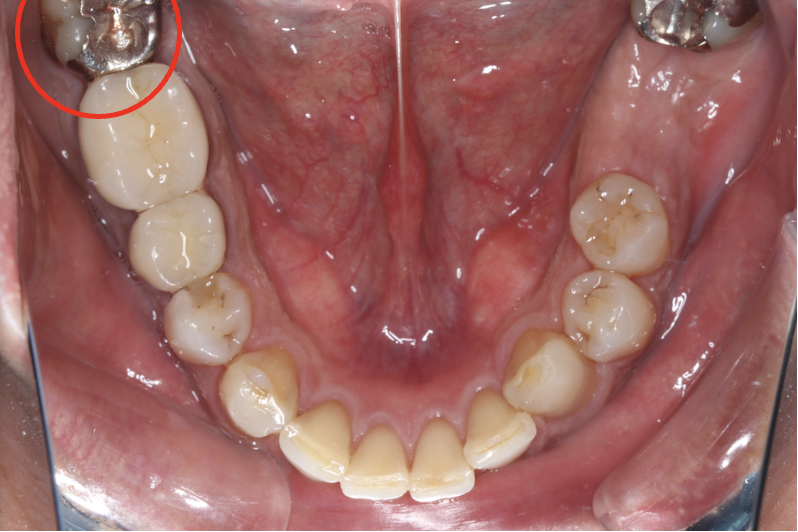

セラミック症例③

年齢30代女性

治療期間1ヶ月

治療内容セラミックインレー

治療箇所右下4番

治療費用100,000円